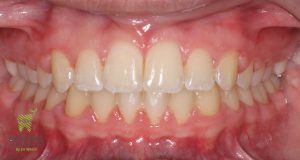

Initial and Final photos correcting a deep bite